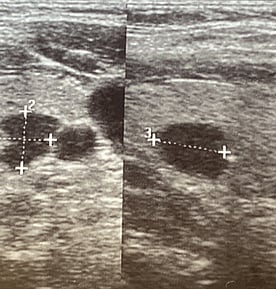

Inactive or less active areas within the thyroid gland appear as "cold" spots on the scan. Cold nodules have reduced or no uptake of the radioactive substance, suggesting lower metabolic activity which further implies an inactive gland indicating benign or malignant growths. Most thyroid nodules are cold and may require further investigation, such as fine needle aspiration biopsy (FNA), to assess for malignancy.